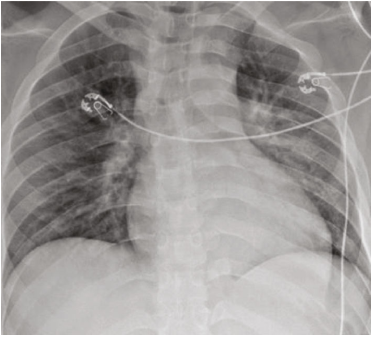

入院时的全血细胞计数显示白细胞为11200/mcL,中性粒细胞计数升高。患者患有急性肾功能衰竭,血尿素氮和肌酐分别为28mg/dL和1.69mg/dL。降钙素原升高至2.18 ng/mL。胸部X光片显示双侧下叶浸润(图2),患者因社区获得性肺炎接受多西环素治疗。

图2